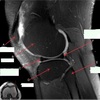

11

Q

What is letter A?

A

ANTERIOR LABRUM

How well did you know this?

1

Not at all

2

3

4

5